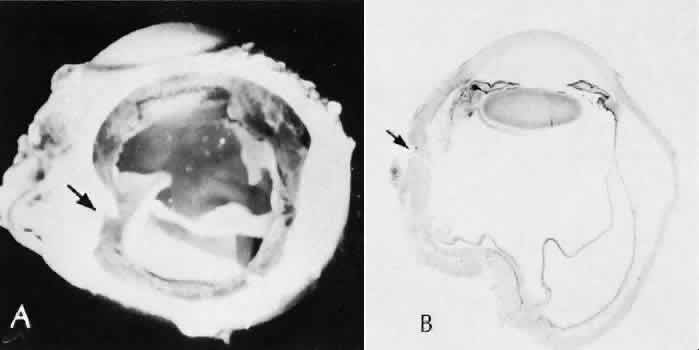

Fig. 31. A case of choroidal detachment. A. By fundus reflex, a large dome-shaped mass can be seen originating from the choroid. The differential diagnosis would include uveal malignant melanoma. In this case, the clinical findings were due to choroidal detachment from the sclera because of fluid accumulating in the suprachoroidal space following cataract surgery. B. The histologic section from another case of choroidal detachment illustrates the location (arrow) and extent of the detachment. In this case the detachment extends to the region of the ciliary body limited anteriorly by the attachment of the choroid to the scleral spur. The displacement of the ciliary body will result in apparent shallowing of the anterior chamber. (Hematoxylin-eosin stain; × 6.)